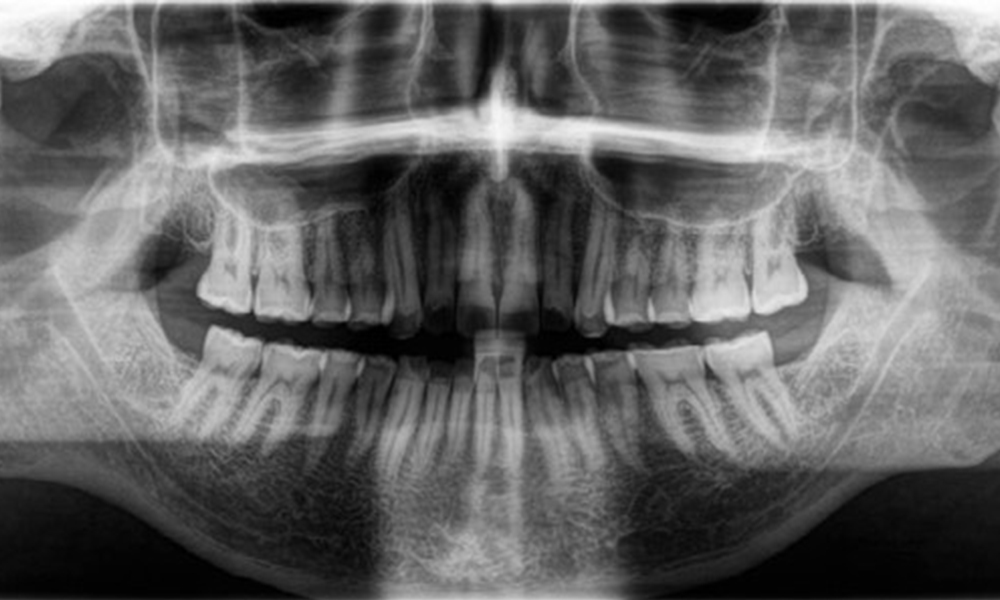

Radiologischer Befund

Es zeigt sich ein vollbezahntes, kariesfreies Erwachsenengebiss ohne radiologisch erkennbaren Knochenabbau (Abb. 6). Radiologischer Schmelz- und Höckerverlust sind insbesondere an 36 und 37 festzustellen.

Panoramaschichtaufnahme

Abb. 6: Panoramaschichtaufnahme, © Dr. R. Krapf